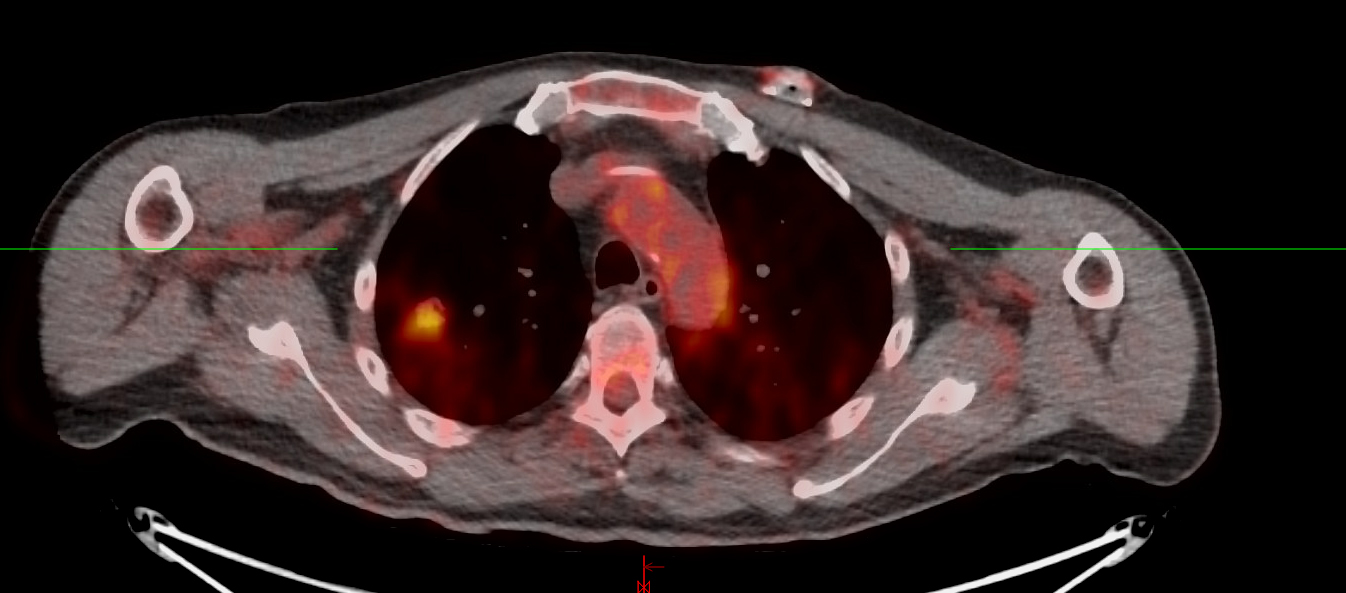

A magnetic resonance imaging (MRI) of William Brtis' bladder.

When William went to Northwestern Medicine Palos Hospital for tests, his care team found a mass in his bladder. Pathologists diagnosed him with an aggressive form of bladder cancer: muscle-invasive, high-grade urothelial carcinoma.

Six days later, William found out he also had right lung adenocarcinoma, a form of lung cancer.

First, to treat the bladder cancer, William had surgery to remove the mass, followed by several weeks of chemotherapy. Later, surgeons at Robert H. Lurie Comprehensive Cancer Center of Northwestern University removed William's entire bladder and prostate. This put William in bladder cancer remission.

After recovering from surgery, William's care transitioned to Haider Ali Shirazi, MD, a radiation oncologist at Northwestern Medicine, to focus on the lung cancer diagnosis. He began a regimen that included both chemotherapy and daily intensity-modulated radiation therapy (IMRT) for his lungs. IMRT, which concentrates the amount of radiation to the tumor, minimizes the potential damage to other parts of the body and organs, which can reduce side effects and help protect healthy cells.